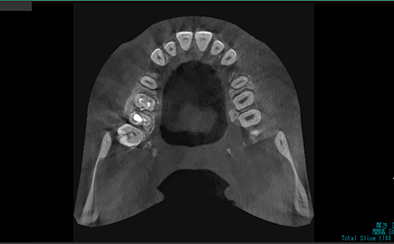

精密な検査・診断

矯正治療を行う前に、各種検査を実施して患者さんの状態を確認いたします。事前検査の結果は治療計画の作成に重要であり、当院ではCTやマイクロスコープなど先端機器を用いて精度高く実施しております。検査結果をもとに、日本口腔外科学会専門医が丁寧に診断して治療計画を作成させていただきます。

アキシャル像

コロナル像

サジタル像

歯科用CT